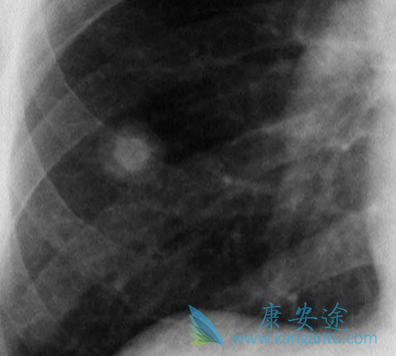

一般肺癌发现都比较晚,很多病人和家属都不敢信息,因为好好的一个人就被确诊为肺癌晚期了,实在难以接受,今天小编给大家讲下肺癌晚期症状,以及治疗。肺癌疼痛,声音嘶哑,面、颈部水肿,气促、胸腔积液等都是常见的肺癌晚期症状

肺癌能治好吗?就晚期肺癌的治疗方法而言,手术切除的可能性很低,临床上晚期肺癌的主要治疗方法有放疗、化疗、中医药治疗。虽经手术但肿块无法切除,虽然经过放化疗但肿块未完全消失,或转移灶明显无法再进行手术、放化疗。而服中药数年,肿块变化不大,或缩小、或稍有增大,但生存期延长、生存质量提高,这也是“带癌生存”的最大特点。